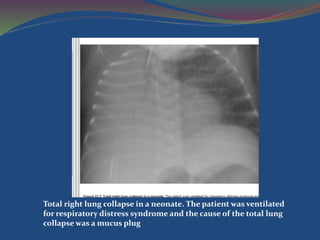

Total right lung collapse in a neonate. The patient was ventilated

for respiratory distress syndrome and the cause of the total lung

collapse was a mucus plug

Total right lungcollapse in a neonate. The patient was ventilated for respiratory distress syndrome and the cause of the total lung collapse was a mucus plug